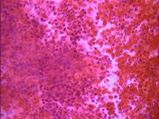

La histopatologia Nº 02-189, realizada en la Cátedra de Anatomía Patológica General y BMF de la Facultad de Odontología, informó que se trataba de epitelio malpighiano con francas hendiduras entre epitelio integro y el corion. El conjuntivo presentaba infiltrado inflamatorio moderado linfoplasmocitario con eosinófilos escasos e hiperplasia endotelial vascular (Foto 5)

Foto 5 Desprendimiento in toto del tejido conjuntivo y presencia de neovasos

“En suma: lesión erosiva ampollar cuya morfología orienta a penfigoide de las membranas mucosas”

El estudio histopatológico (Nº 03-129) realizado en la Cátedra de Anatomía Patológica General y BMF de la Facultad de Odontología, informó que se trataba de una ampolla subepitelial. El epitelio se mantenía en áreas adosado a la membrana basal. El conjuntivo presentaba un infiltrado inflamatorio linfocitario, con neutrófilos, plasmocitos, abundantes mastocitos y neovasos (Fotos 8 – 10).

Foto 8 Hendidura entre epitelio de cubierta y tejido conjuntivo. Ampolla subepitelial